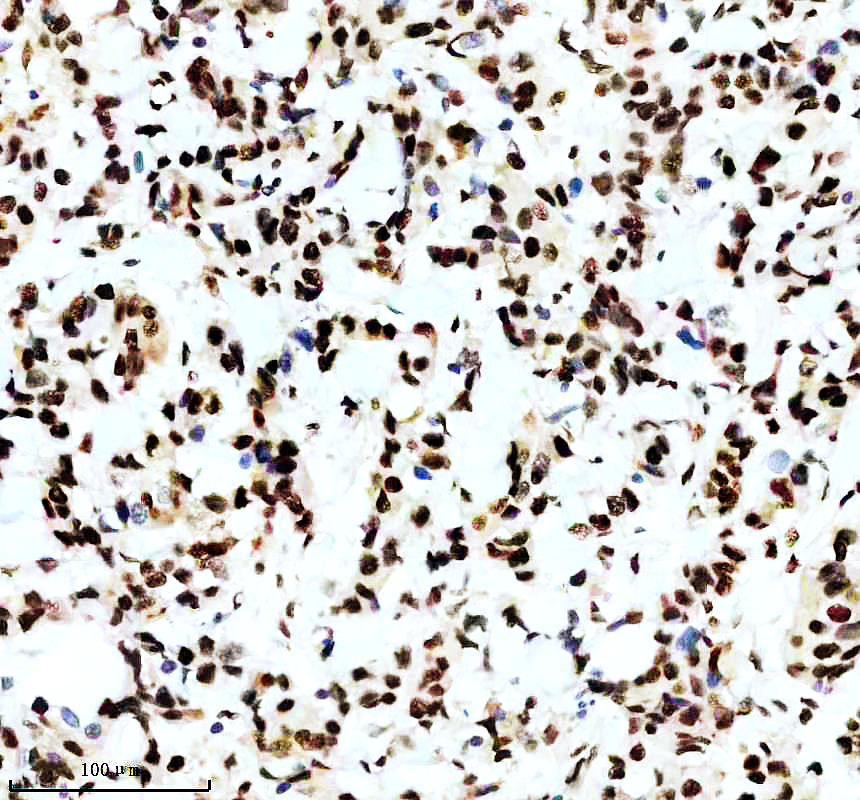

IHC analysis of P-MDM2 using anti-P-MDM2 antibody (P00054-2).

P-MDM2 was detected in a paraffin-embedded section of human breast cancer tissue. The tissue section was incubated with rabbit anti-P-MDM2 Antibody (P00054-2) at a dilution of 1:200 and developed using HRP Conjugated Rabbit IgG Super Vision Assay Kit (Catalog # SV0002) with DAB (Catalog # AR1027) as the chromogen.